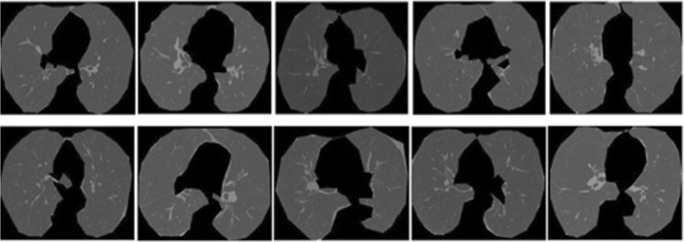

Fig. 5.

Images obtained from ELCAP lung database for 10 different groups

The second dataset is obtained from ELCAP lung database. Out of the four repositories available in (http://www.via.cornell.edu/lungdb.html), we selected W0011-W0020 repository. It had CT scan images for 10 different groups and image classification will be done for these 10 groups. Each slice is of 1.25 mm thickness and is obtained in a single breath hold using CT scan. The dataset is also provided with the location of nodules in the lungs of the patient. The details of these two datasets are given in Table 2. Images of patients from four different groups of dataset 1 and 10 different groups of dataset 2 are given in Figs. 4 and 5 respectively.